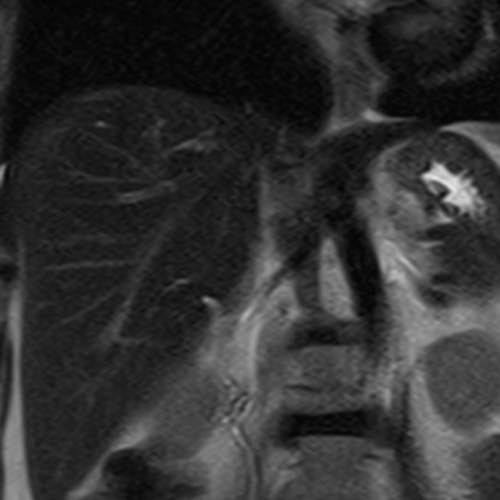

Cet examen est réalisé pour analyser le foie.

Cette examen permets d’analyser le parenchyme hépatique et les vaisseaux portes. Il permet de diagnostique les angiomes, HNF, adénomes, métatases, cholangio carcinome.